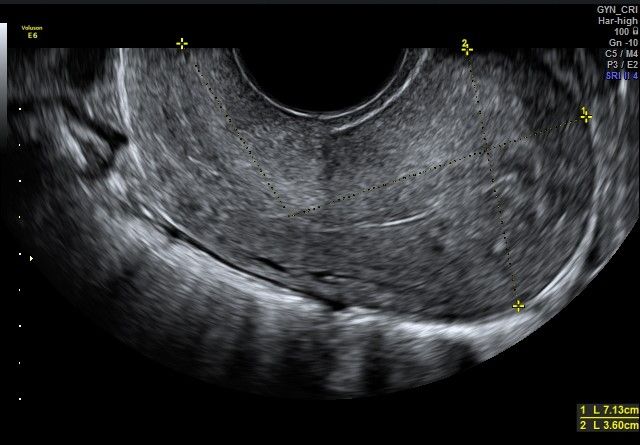

diagnostica ecografica tranvaginale con eco color doppler di I e II livello e transaddominale

Foto e video